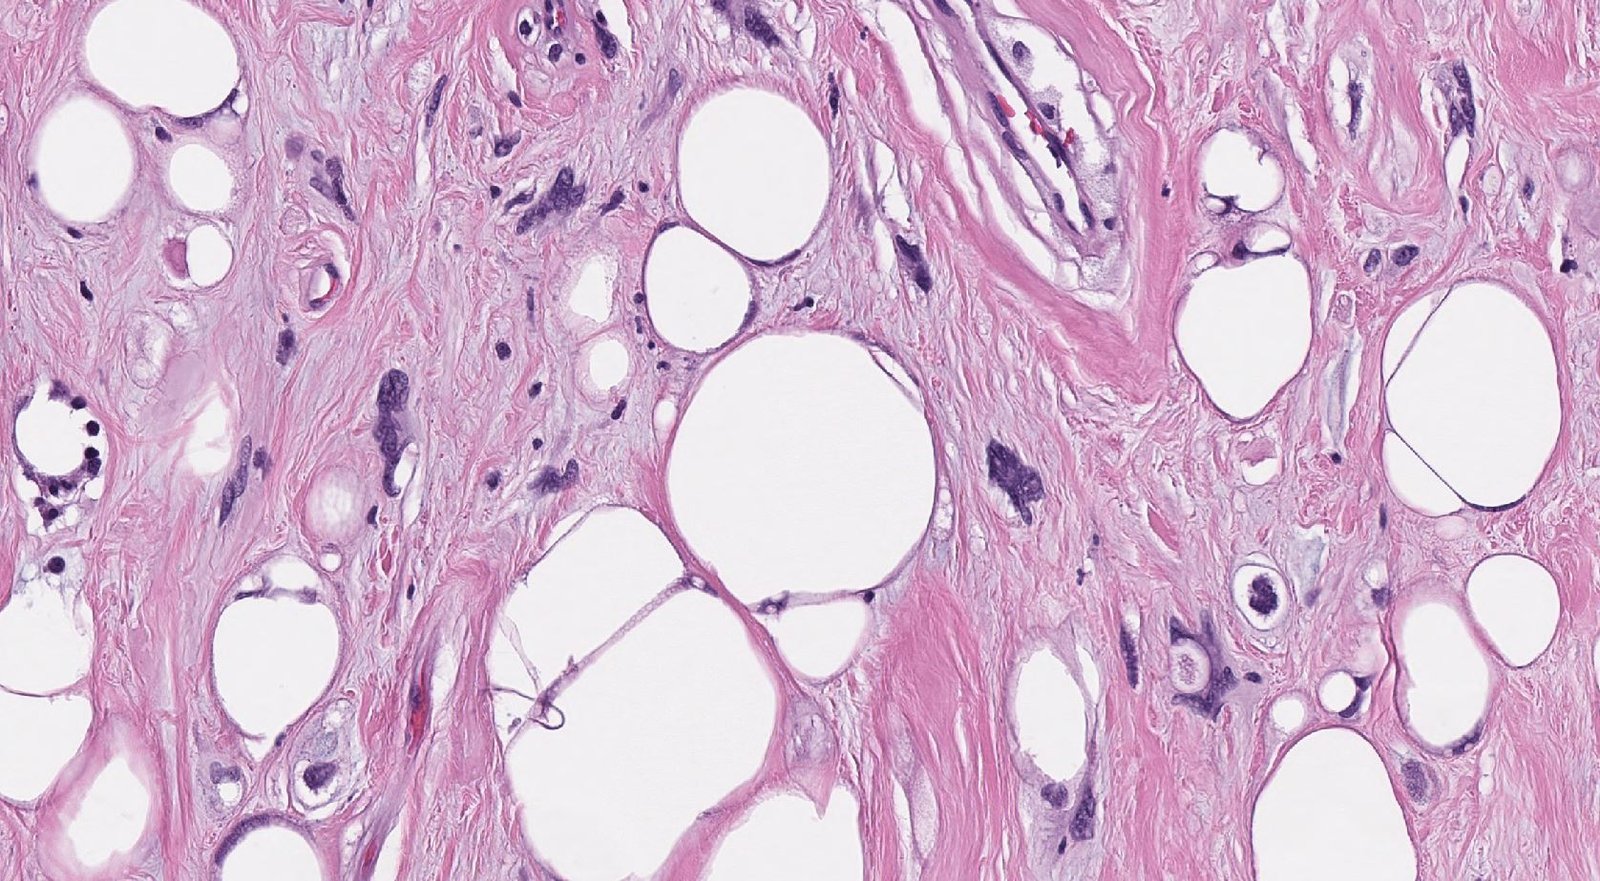

Case: RetroperitonealMass

Final Diagnosis: